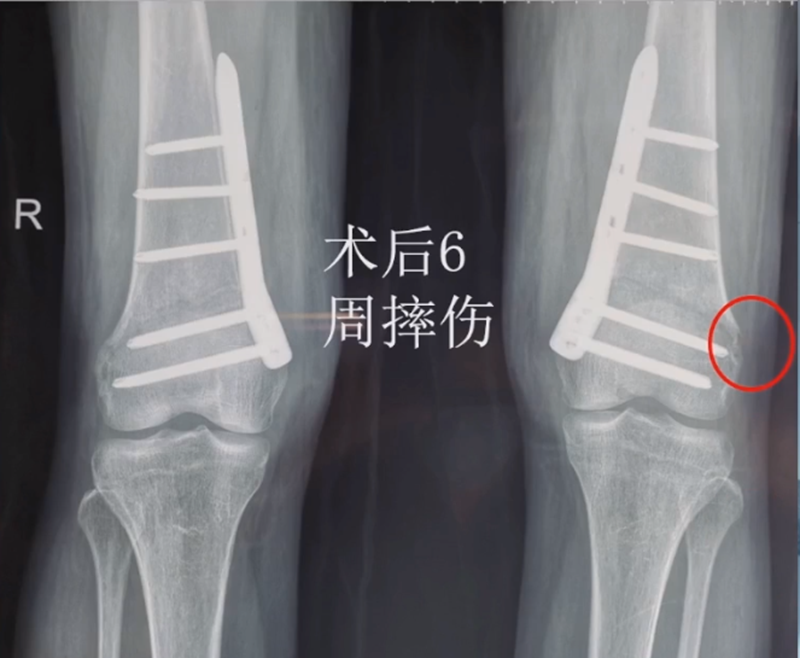

病例,X患者,女,双侧外翻膝,行双侧DFO。

术后6周摔伤,一侧出现膝内翻。

影像学检查显示左侧出现合页断裂。

进行翻修,术前力线显示内翻。

术后10周复查,力线较好。